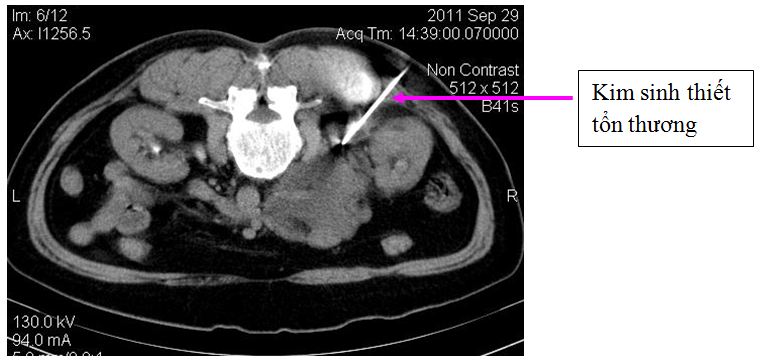

Ngày 29 tháng 9 sinh thiết u sau phúc mạc dưới hướng dẫn của chụp cắt lớp vi tính, cắt 4 mảnh làm sinh thiết

Bệnh nhân và gia đình bệnh nhân rất hoang mang lo lắng. Bệnh nhân đã được hội chẩn với bác sỹ chuyên khoa ngoại để xem xét khả năng phẫu thuật cắt u hoặc sinh thiết u. Ý kiến của các phẫu thuật viên: vì tổn thương trên hình ảnh cắt lớp vi tính rất rộng, ngay sát các mạch máu lớn nên phẫu thuật lấy hết tổn thương rất khó, nên tiến hành sinh thiết tổn thương

+ Chúng tôi quyết định sẽ sinh thiết tổn thương dưới hướng dẫn của chụp cắt lớp vi tính lần 2